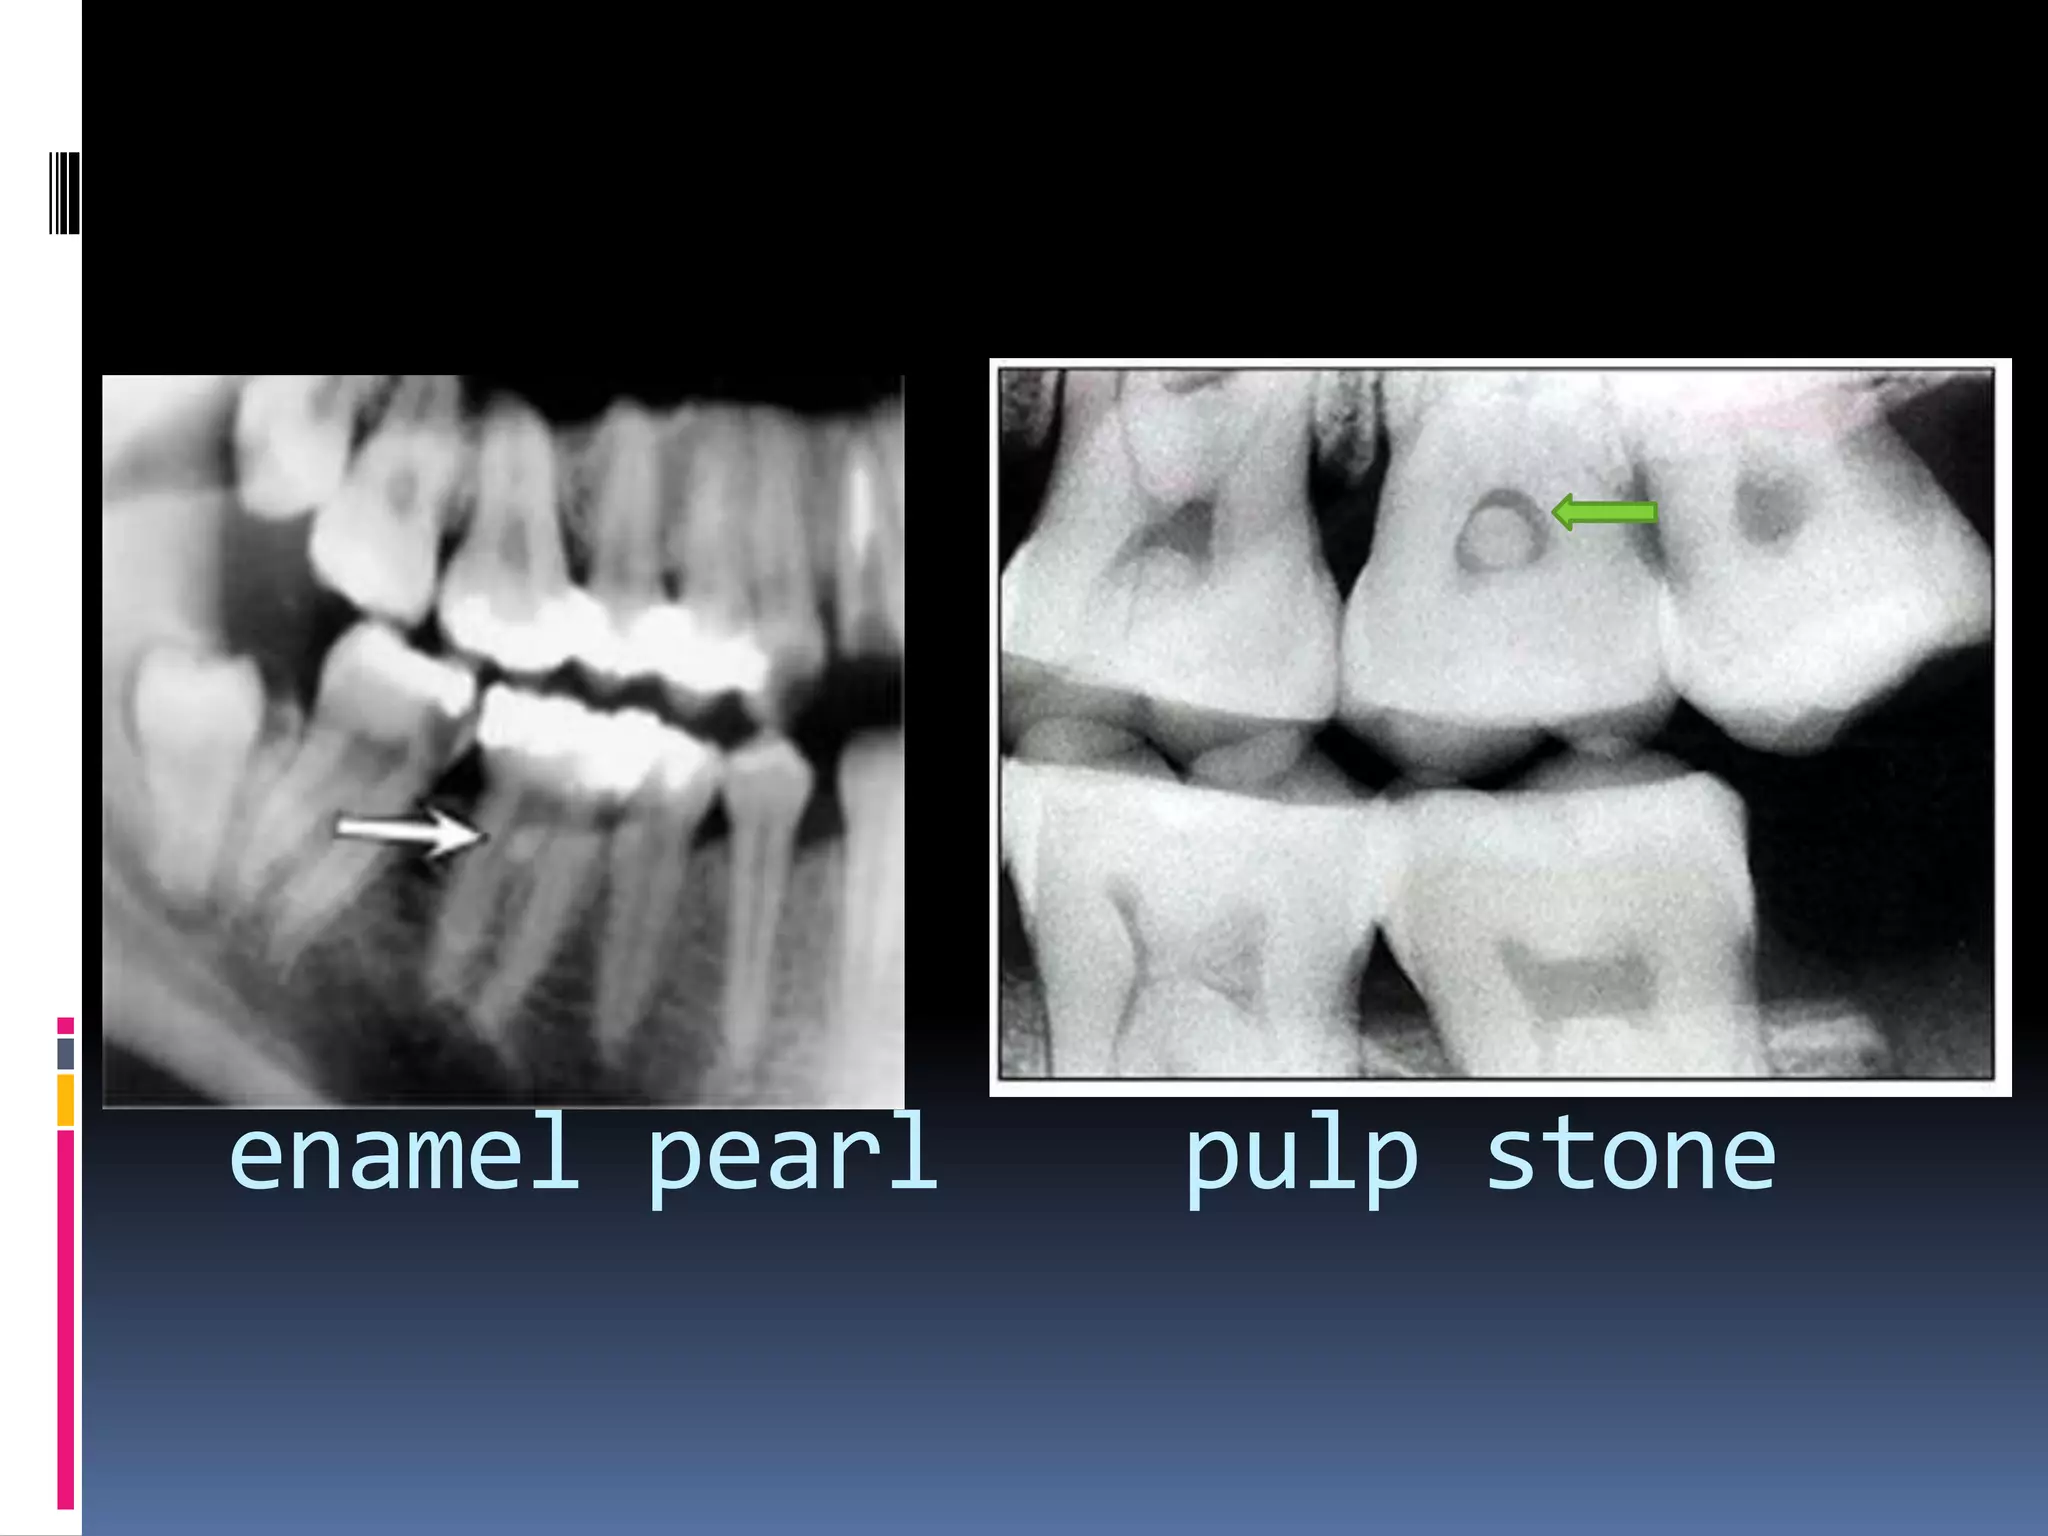

Ectopic enamel

i)Enamel pearl /enameloma:

Hemispheric structures consist entirly of

enamel/ contain dentin & pulp.

 Due to prolonged contact b/t hertwig’s root

sheath & developing dentin inducing enamel

formation.

 1-4 epithelial pearls.

> in root furcation /near CEJ.

 R/F – well defined radiopaque nodules along

root surface.(CEJ)

enamel pearl pulp stone

Pulp stones